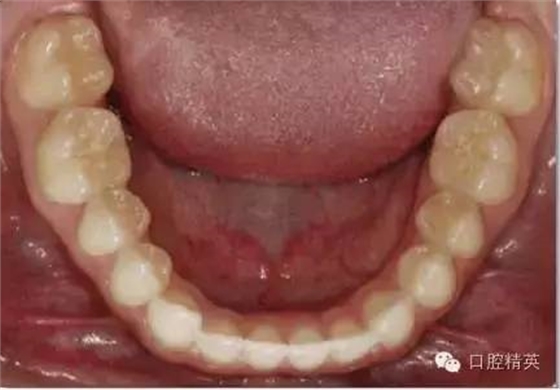

下頜合面照

合面觀

1:2 (1:3) Mag nification

需要使用拉鉤及反光板

•合面照需要使用成像清晰的反光鏡。請拍攝時使用拉鉤,否則軟組織會包裹鏡面阻擋牙面。

•中切牙唇面應位于相片邊緣處。

•取景時應盡量減少反光鏡邊緣和嘴唇的暴露。患者的鼻子或非反光成像的牙齒應不要位于畫面中。

•輕吹反光鏡或將反光鏡泡于溫水中能減少鏡面霧氣的形成。

•相機應位于反光鏡鏡面45°左右處。反光鏡中的成像應為牙齒的舌側及唇側都可見。一個過淺的拍照角會使得唇頰面及舌腭面的楔狀隙角度記錄有誤。

•盡量暴露所有的牙齒。至少應包括從中切牙到第二磨牙近中。前牙應始終能清晰成像。

•照片中應能清晰顯示下切牙邊緣位置、唇頰側及舌腭側楔狀隙。

•此照片可以從患者正前方拍攝(鏡頭稍向下斜,患者頭部向后靠)。直接位于病人后方拍攝會非常困難。

•患者舌頭應盡量避免遮擋牙面,應囑患者盡量后縮舌頭,或用反光鏡子擋住舌頭。

•焦點位于反光鏡中的雙尖牙。

•開始先使用1:2 (1:3)放大倍率,然后調整放大倍率以拍攝下頜牙弓作者:牙醫(yī)加加

•取景時應盡量減少反光鏡邊緣和嘴唇的暴露?;颊叩谋亲踊蚍欠垂獬上竦难例X應不要位于畫面中。

•開始先使用1:2 (1:3)放大倍率,然后調整放大倍率以拍攝下頜牙弓